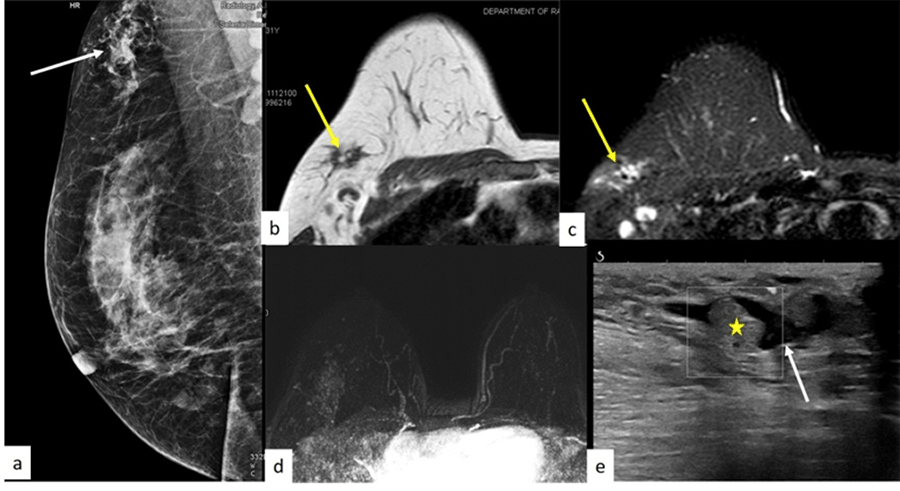

A bilateral mammogram with sonographic assessment was used to complete the triple assessment. There was mammographic asymmetry in the upper quadrant of the right breast (Figure 2A). Ultrasound depicted normal fibro-glandular tissue with duct ectasia in the axillary tail region. Few echogenic circumscribed echogenic masses with no internal vascularity were seen within the ducts (Figure 2E). A probability of duct ectasia with intraductal papilloma in the axillary tail region was made, and contrast-enhanced magnetic resonance imaging (CE MRI) was subsequently done for better delineation. On CE MRI, there was non-mass enhancement with a type 2 kinetic curve in the UOQ of the right breast measuring 5.0 × 2.3 cm from the 9 to 11 o’clock position, which was reaching up to the skin. The lesion was heterogeneously hyperintense on T2 STIR and showed mild diffusion restriction (Figure 2B, Figure 2C, and Figure 2D). It was classified as BIRADS IVc, and an ultrasound-guided core needle biopsy was performed. This biopsy showed benign parenchyma with foci of chronic inflammation and stromal hyalinization.

Figure 2. Mediolateral Oblique (MLO) View of Mammogram of the Right Breast. Published with Permission

A) Asymmetric density at right axillary tail location (arrow)—density does not have any spiculation or microcalcification; B) lesion (arrow) is hypointense on T1W on MRI; C) and hyperintense on STIR images—D) no enhancement on subtracted maximum intensity projection (MIP) contrast-enhanced images. E) High-resolution focused ultrasound image of abnormality reveals dilated anechoic tubular channels (arrow), suggesting duct ectasia. Echogenic intraductal content (asterisk) is likely debris due to flow demonstration on color Doppler interrogation (shown in box).